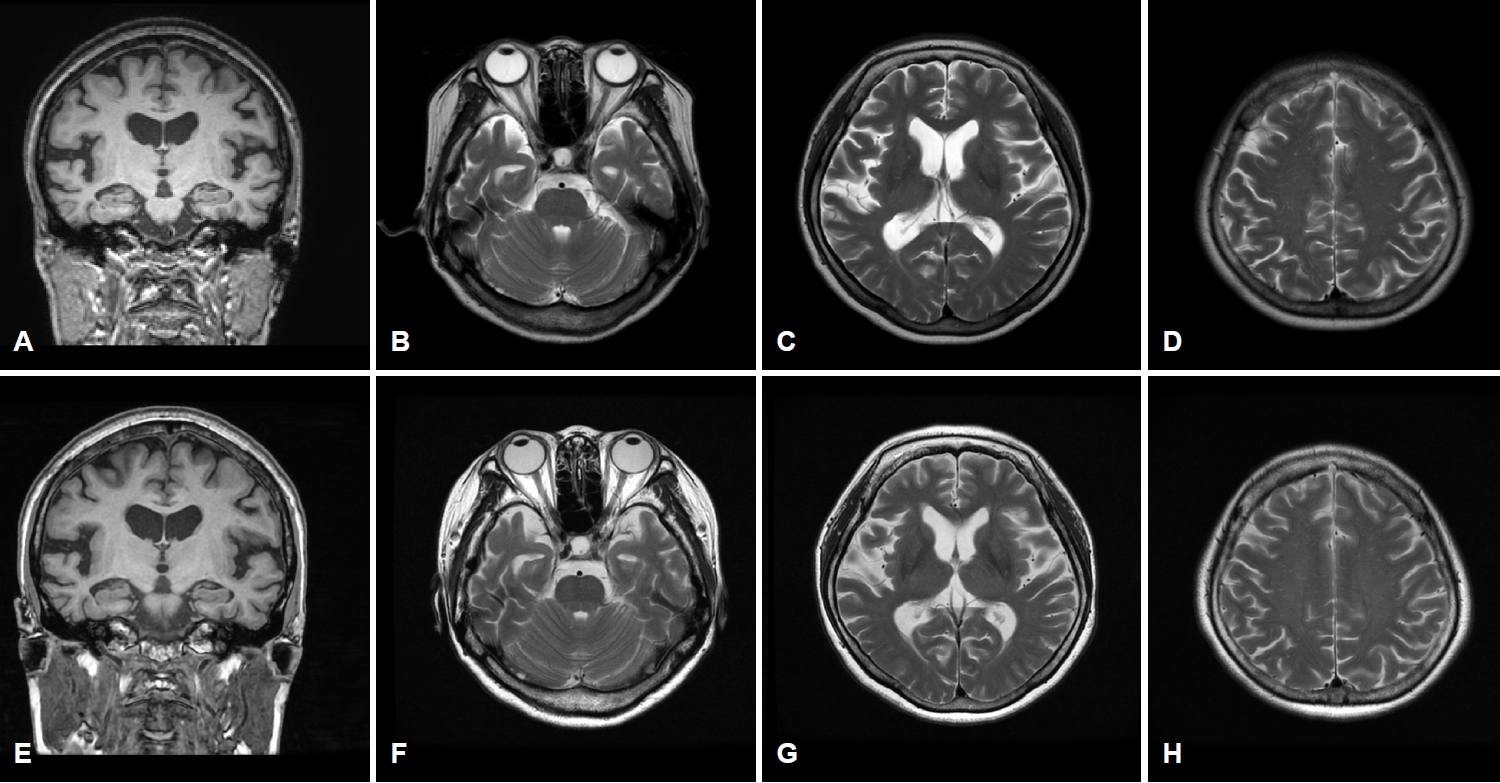

6년의 학력을 가진 오른손잡이인 61세 여자 환자가 서서히 시작된 기억력 및 언어능력저하로 지역 치매안심센터를 경유하여 2019년 6월 본원 신경과로 진료가 의뢰되었다. 한 달에 1-2번 정도 왕래하는 딸에 의하면, 환자는 약 1년 전부터 자신이 했던 일을 반복적으로 잊어버리는 경우가 많았고 물건의 위치를 기억하지 못하였다. 오래된 기억은 문제가 없었다. 그리고 대화할 때 단어를 쉽게 떠올리지 못하는 모습을 보였다. 길 찾기에는 문제가 없었고 성격 변화도 없었다. 집안 살림을 스스로 할 수 있었다. 과거병력과 치매 가족력에서 특이 소견은 없었다. 신경계진찰에서 운동, 감각 및 심부건반사는 정상이었다. 한국판간이정신상태검사(Korean-Mini Mental Status Examination, K-MMSE)는 17점, 임상치매평가척도(Clinical Dementia Rating, CDR)는 0.5점 그리고 임상 치매평가척도-총합점수(CDR-Sum of boxes, CDR-SB)는 1.5점이었다. 비문해노인특성반영 인지기능검사(Literacy Independent Cognitive Assessment)에서 나이와 학력에 비하여 기억력, 언어기능, 시공간기능, 집행기능 및 계산기능의 저하 소견이 관찰되었다. 뇌 자기공명영상(magnetic resonance imaging, MRI)에서는 전두측두엽과 해마의 위축이 관찰되었는데 우측에서 더 명확한 변화가 관찰되었다(Fig. 1-A-D). 18F-flutemetamol 아밀로이드양성자단층촬영(PET)도 시행되었다. 18F-flutemetamol 주입 10분 후에 얻은 초기 동적영상에서는 우측 전두측두두 정엽의 기능저하 소견이 관찰되었으나(Fig. 2-A-C) [4,5], 18F-flutemetamol 주입 90분 후 촬영한 지연 영상에서는 아밀로이드 침착이 보이지 않았다(Fig. 3-A-C; global standardized uptake value ratios, 1.33; cut-off value, 1.50). 뇌척수액에서 시행한 생물표지자 분석(INNOTEST ELISA kit; Fujirebio Diagnostics, Ghent, Belgium)에서 Aβ42 385 pg/mL (cut off value, 481 pg/mL), 총 타우(total tau) 524 pg/mL (cut off value, 326 pg/mL), p타우(p-tau)181 68 pg/mL (cut off value, 57 pg/mL)의 결과를 얻었다[6]. 뇌 PET검사에서 아밀로이드 축적을 보이지 않았으나, 환자의 임상 양상, 신경심리검사, 뇌 MRI, PET 초기 동적영상 및 뇌척수액생물표지자검사 결과를 종합할 때, 환자는 아밀로이드 양성, 타우 양성 및 신경변성 양성 상태의 조기발병 기억상실다중영역경도인지장애로 진단하였다. 환자는 검사 이후 1년 사이에 인지기능과 일상활동의 급격한 악화를 보였다. 환자는 전날 외식한 것을 기억하지 못하였다. 오후 3시에 남편에게 저녁을 먹으라고 차리기도 하였으며, 세탁한 것과 그렇지 않은 것을 구분하지 못하였다. 전혀 의사소통이 되지 않고 엉뚱한 행동을 하였다. 말을 할 때도 더듬거리면서 단어를 잘 말하지 못하였고 말수가 점차 줄어들었다. 집 근처에서조차도 방향을 헷갈려 하고 집안에서도 길을 헤매게 되었다. 금전 및 은행 업무는 전혀 할 수 없었다. 원래는 사교적인 성격이었으나 전혀 모임에 나가지 않았고 남편이 외출하면 불안해하였다. 반찬도 잘 못하고 하더라도 양이나 간 조절이 안되었다. 2020년 7월에 시행한 신경계진찰에서 운동, 감각 및 심부건반사는 정상이었다. K-MMSE는 13점, CDR은 2점, CDR-SB는 10점이었다. 뇌 MRI에서는 1년 전에 보이던 뇌위축이 더 진행된 소견을 보였다(Fig. 1-E-H). 18F-flutemetamol 아밀로이드 PET검사상, 초기 동적영상에서는 우측 전두엽과 양측 측두두정엽의 기능저하 소견이 관찰되었으나(Fig. 2-D-F), 지연영상에서는 여전히 아밀로이드 침착이 보이지 않았다(Fig. 3-D-F; global standardized uptake value ratios, 1.22). 환자는 이후로도 점차 악화되는 경과를 보여 2021년 4월에 시행한 검사에서는 K-MMSE 10점, CDR 2점, CDR-SB 11점을 기록하였다. 환자의 아포지단백질E (apolipoprotein E) 유전자아형은 ε4/ε4였다. 가족력은 없었지만 조기발병 치매 환자에서 비전형적인 알츠하이머치매의 생물표지자 발현을 보여 시행한 유전자검사(targeted exome sequencing; Dxome, Seongnam, Korea)에서 아밀로이드전구단백질(amyloid precursor protein, APP), 프레세닐린-1 (presenilin [PS]-1) 그리고 프레세닐린 -2 (PS-2)에는 원인 유전자변이(causative gene mutation)가 없음을 확인하였다.

61세 여자 환자는 3년여에 걸쳐 기억장애를 포함한 여러 영역의 인지장애와 이로 인한 일상활동장애를 보였으며, 증상이 서서히 발생하여 지속해서 악화하였다. 뇌 MRI에서의 우측 전두측두엽의 뇌위축과 아밀로이드PET의 조기 동적영상에서 전두측두두정엽의 대사 저하 양상이 관찰되는 것은 감별진단으로 알츠하이머치매 외에 전두측두치매나 피질기저핵변성도 고려할 수 있다. 그러나 3년간의 임상 경과로 미루어 환자는 초기에 현저한 기억저하를 보였고, 두드러진 이상행동을 보이지 않았으며 운동질환과 관련된 신경계 이상을 보이지 않아 전두측두치매나 피질기저핵변성보다는 알츠하이머치매가 보다 적합한 임상진단명으로 생각되었다. 뇌척수액 검사에서는 Aβ42 감소, 총 타우 증가, p-tau181 증가가 관찰되어 알츠하이머병 병태생리 과정에 대한 증거가 생물표지자로 일치하는 소견이었으나 아밀로이드PET에서 음성이 관찰되었다. 환자는 PET-/CSF+ 알츠하이머치매의 가능성을 가장 높게 생각하였으나 1년 후 중기 치매 진행된 상태에서도 아밀로이드PET 결과가 여전히 음성으로 관찰되어 환자의 최종적인 진단명이 알츠하이머병인지 또는 알츠하이머병 외에 다른 병이 동반되어 있는지에 대해서는 뇌의 병리조직검사 결과가 뒷받침되어야 하는 제한점을 가진 증례이다.